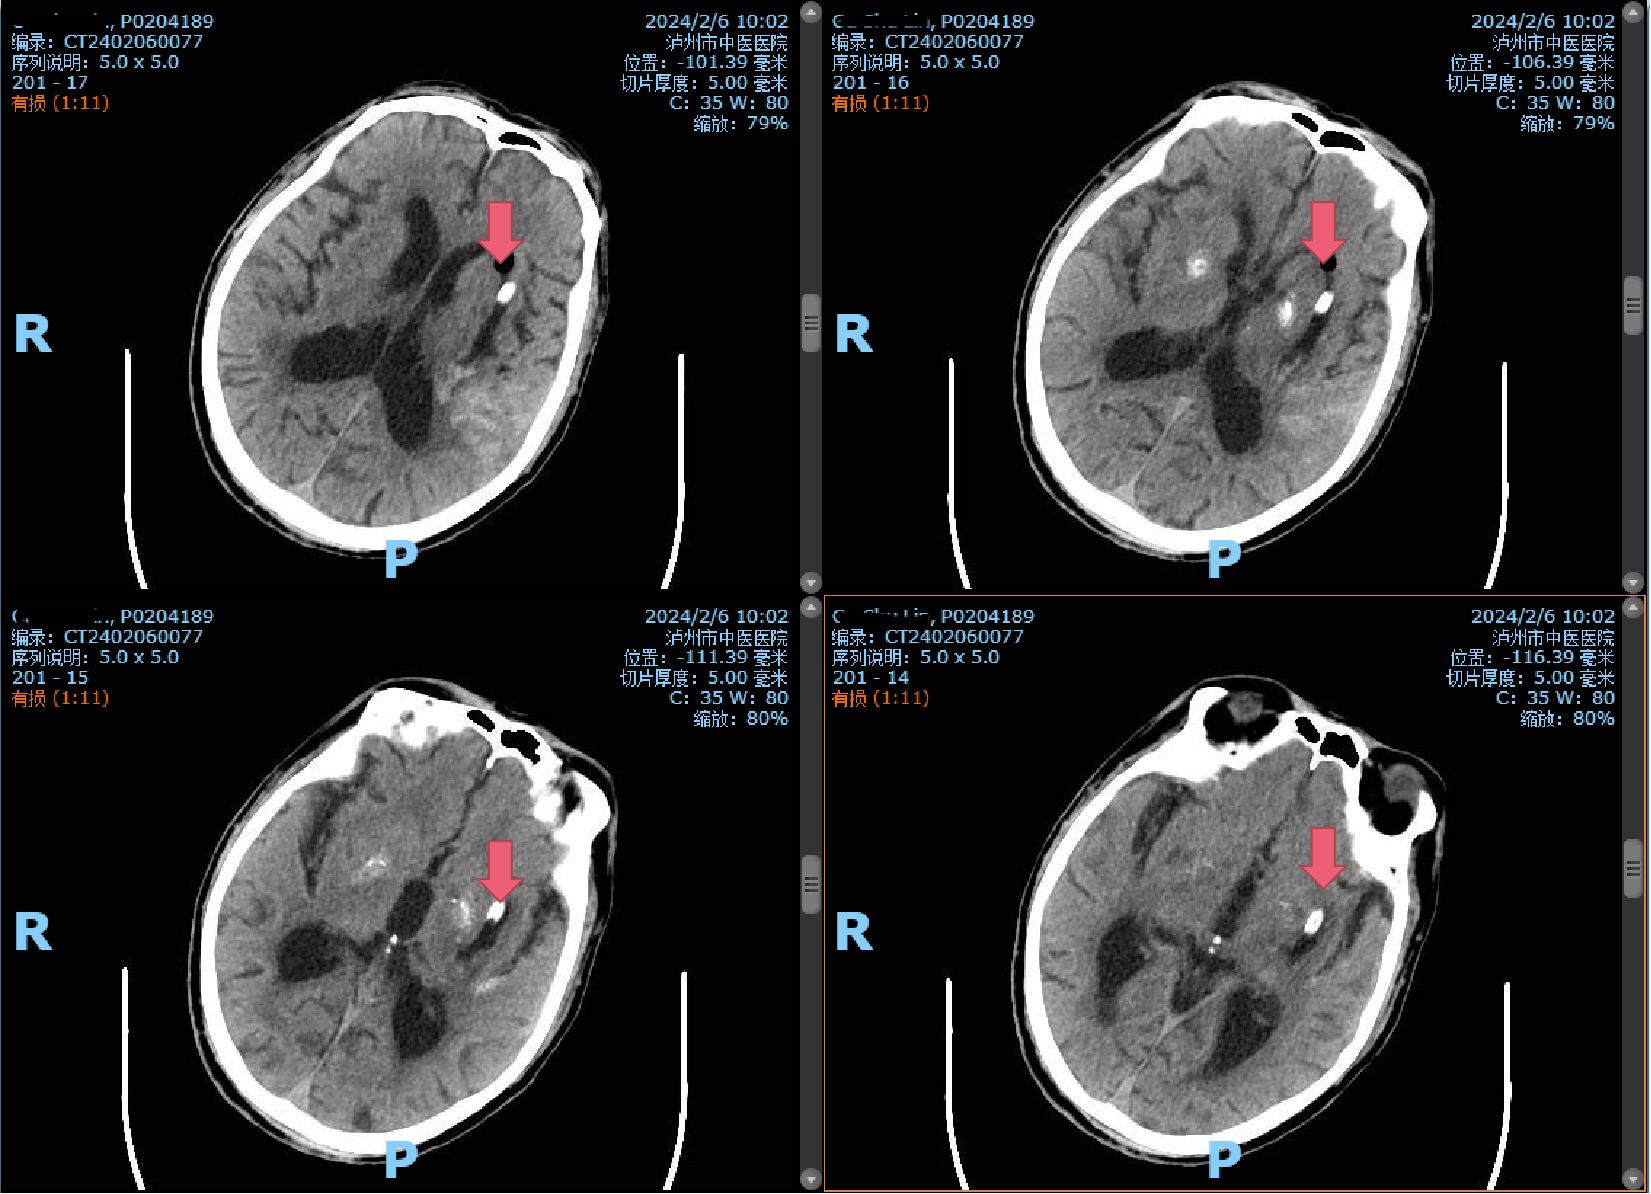

術(shù)前CT:左側(cè)基底節(jié)區(qū)腦出血伴血腫形成(紅色箭頭所指)

時間第一,生命至上?;颊呷朐汉笾苯咏?jīng)急救通道,完善頭顱CT,提示腦出血,病情危重,立即及時、安全地送到了市中醫(yī)院重癥監(jiān)護(hù)室,并通知神經(jīng)外科。入院后由首診醫(yī)師曹飛副主任醫(yī)師接診。經(jīng)過仔細(xì)詢問病史、查體發(fā)現(xiàn)患者昏迷不醒,呼之不應(yīng)、無言語。雙瞳形圓不等大,向左凝視,左側(cè)瞳孔直徑約2.5mm,對光反射消失;右側(cè)瞳孔直徑約3mm,對光反射消失。右側(cè)肢體肌肉張力高,病理征陽性;結(jié)合CT片后診斷為:左側(cè)基底節(jié)區(qū)腦出血伴血腫形成。